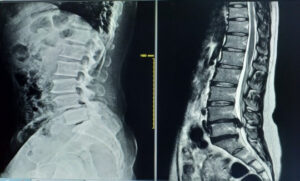

整形外科は、レントゲンやMRIを用いた「画像診断」のスペシャリストです。

弱点: 筋肉のコリ、筋膜の癒着、微細な神経の圧迫などは画像に映りません。痛みがあるのに「異常なし」と言われるのは、原因が筋肉や姿勢にあるからです。